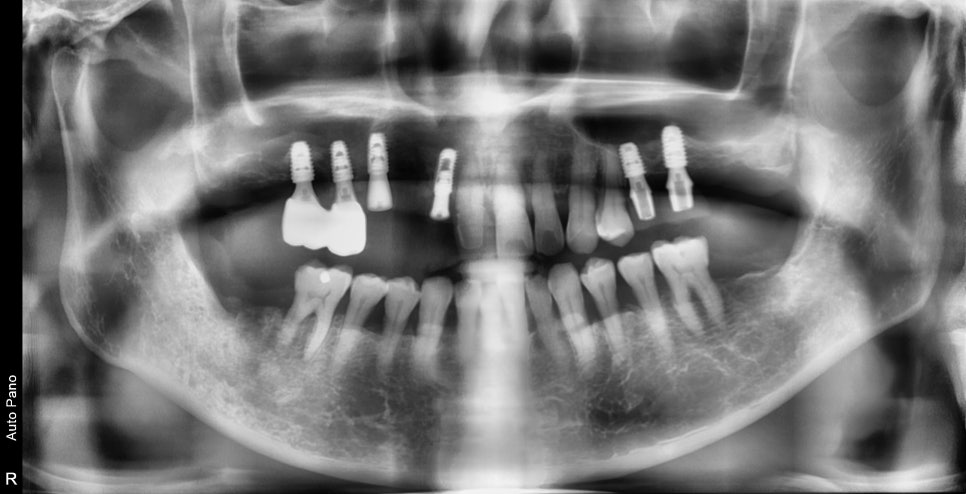

2차 수술 후 엑스레이 사진입니다.

최종 보철물까지 진행은 아직 안 되었지만

치주염이 심한 환자분들 중에서는

발치 당일 임플란트의 수술이 힘든 경우도 종종 있습니다.

웬만하면 마취된 당일에 수술까지 하는 것이 저나 환자분께 편하지만

무리한 진행보단 안정성을 택하는 것이 장기적인 관점에서는 훨씬 좋습니다

이 케이스는 나중에 보철이 완성되면 다시 설명하는 시간을 갖도록 하겠습니다^^